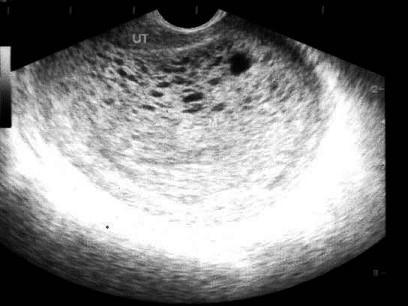

问题 患者女24岁,停经2月余阴道不规则出血数日,阴式B超检查声像图如图所示,应诊断为 ( )

选项 A、宫内积血块 B、先兆流产 C、葡萄胎 D、绒癌 E、早孕

答案 C